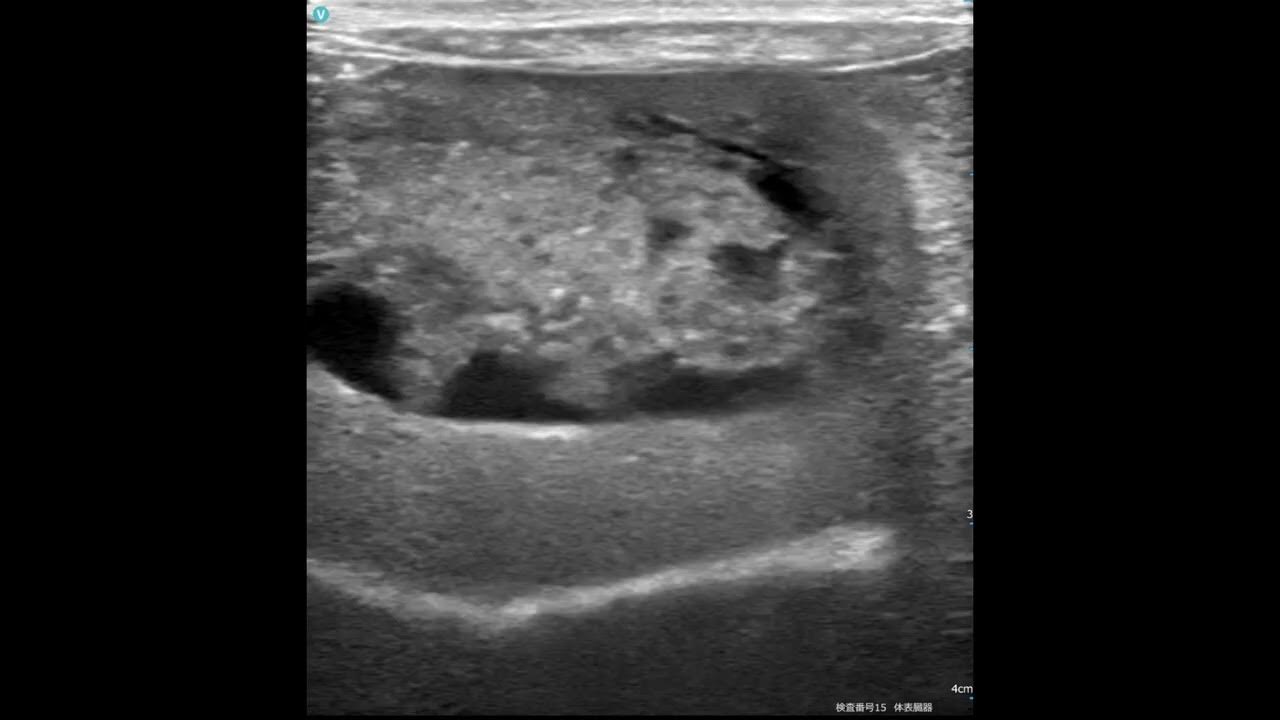

Ultrasonographic features of gall bladder mucocele in dogs when to How Long Do Dogs Live With Gallbladder Mucocele Clinical illness with canine gallbladder mucocele averages ~5 days, although some dogs have vague episodic clinical signs (ie, inappetence,. We do not understand canine gallbladder mucocele well. Dogs with gallbladder mucoceles that undergo cholecystectomy and survive the immediate perioperative period have an excellent long term prognosis. One condition dog owners should be aware of is gallbladder mucocele, a potentially serious. How Long Do Dogs Live With Gallbladder Mucocele.

Gallbladder mucocele ultrasound in Dogs (Canis) Vetlexicon How Long Do Dogs Live With Gallbladder Mucocele The fact that certain dog breeds are predisposed to mucocele. Dogs with gallbladder mucoceles that undergo cholecystectomy and survive the immediate perioperative period have an excellent long term prognosis. Clinical illness with canine gallbladder mucocele averages ~5 days, although some dogs have vague episodic clinical signs (ie, inappetence,. We do not understand canine gallbladder mucocele well. One condition dog owners. How Long Do Dogs Live With Gallbladder Mucocele.

Gallbladder mucocele, Pocket size VS Stationary highend system, echo How Long Do Dogs Live With Gallbladder Mucocele One condition dog owners should be aware of is gallbladder mucocele, a potentially serious issue affecting dogs. The fact that certain dog breeds are predisposed to mucocele. We do not understand canine gallbladder mucocele well. Clinical illness with canine gallbladder mucocele averages ~5 days, although some dogs have vague episodic clinical signs (ie, inappetence,. Dogs with gallbladder mucoceles that undergo. How Long Do Dogs Live With Gallbladder Mucocele.